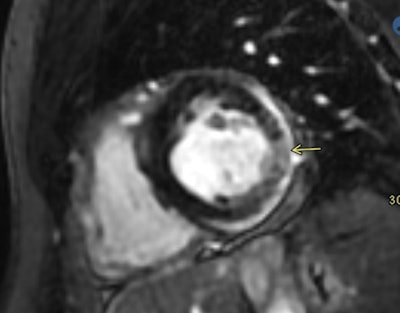

Shaw's team presented cardiac MRI findings from four patients who had received either COVID-19 vaccine and then developed acute myocarditis, diagnosed using cardiac MRI.

As for Dickey and colleagues' case study set, six patients developed cardiac MRI-proven myocarditis soon after receiving either Pfizer or Moderna COVID-19 vaccinations.